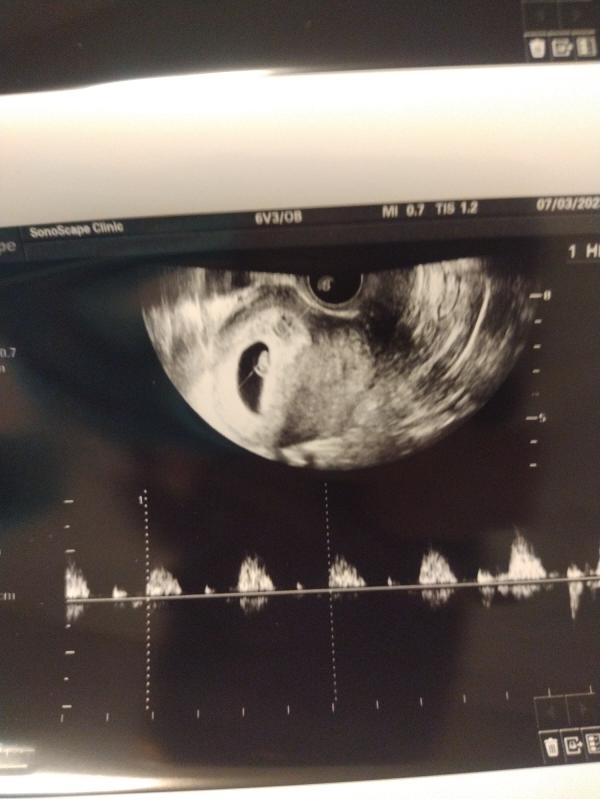

На узи видно масенькую креветуську)))

Написано так: ПЯ СВД 20мм, один эмбрион, КТР 9мм, желточный мешочек 5мм, беременность соответствует сроку 7недель.

Сердцебиение 142 уд/м.